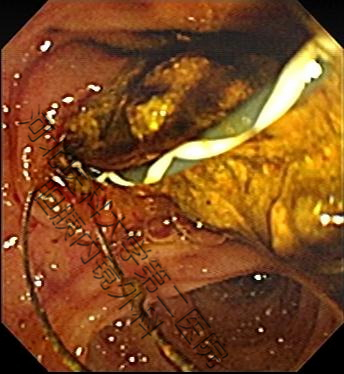

生活中并不缺少美,而是缺少发现美得眼睛,结石虽万恶,但具“自身美”,内镜下的结石也是“横看成岭侧成峰,奇形怪状各不同。簇拥颗粒如桑葚,表面圆滑似卵石。大如蜜枣小如豆,黑黄可见多半棕......”。接下来我们来一起欣赏百张内镜下取石的图片。(所见结石均已从胆总管取出,放入肠道内随大便排出)